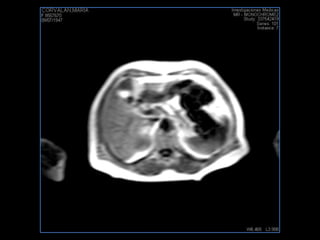

PROTOCOLO abdomen COR T2, AXIAL supresion grasa AX T1 +SAG T2  CON   GADOLINIO :  COR T1+AX T1(DIN) SAT: NO  FASE: RL THK: 6MM  COIL:  GAP: (FACTOR 1.4) 2MM FOV: 40 CM NEX:2 SINCRONIZACION RESPIRATORIA EN 3 O 4 CICLOS ALE

resonancia de abdomen